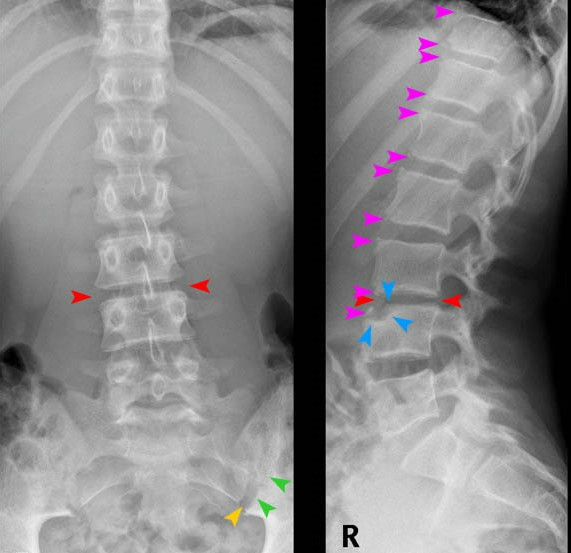

Master the complexities of skeletal imaging in this intensive, two-hour interactive webinar designed for clinicians seeking to sharpen their diagnostic accuracy. Moving beyond basic identification, this session utilizes a deep-dive, case-based approach to explore the nuanced radiographic hallmarks of various osteo-pathologies. Participants will gain practical strategies for differentiating between look-alike conditions across six critical categories: congenital and developmental anomalies, diverse arthritides, complex trauma, neoplastic processes, skeletal infections, and metabolic disorders. By focusing on "real-world" film interpretation, the course ensures you walk away with immediate, actionable clinical reasoning skills.This isn't a passive lecture; it is an inquiry-based workshop where your expertise is a vital part of the curriculum. Attendees are encouraged to actively participate in live sessions, contributing to differential diagnosis discussions and collaborative problem-solving. Whether you are looking to refine your systematic approach to zones of transition or better identify the subtle skeletal manifestations of endocrine imbalances, this webinar provides a dynamic platform to engage with peers and elevate your radiographic proficiency.